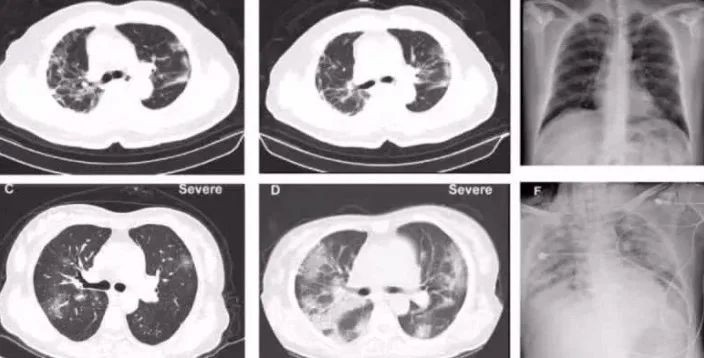

Hình chụp CT phổi của bệnh nhân nhiễm coronavirus.